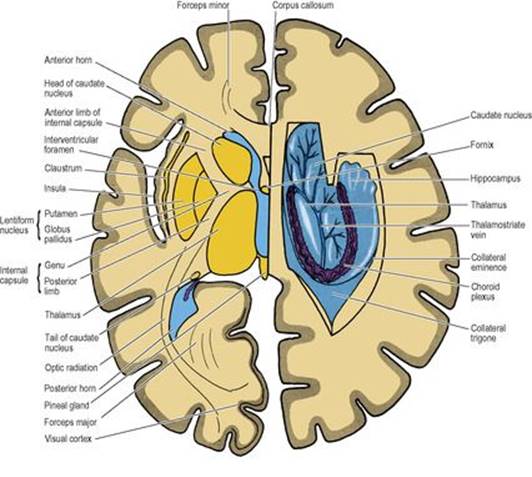

B9780702033957000079/f07-07-9780702033957.jpg is missing

Figure 7.7

Horizontal sections through the cerebral hemispheres, on the left side level with the interventricular foramen and on the right at a slightly higher level with dissection to open up the lateral ventricle.

The claustrum is a thin lamina, circular in outline and curved into a saucer-shape. It lies lateral to the putamen, and although easy to identify in horizontal or coronal sections (Fig. 7.7) its significance is unknown.

The internal capsule consists of afferent fibres passing up to the cortex from cell bodies in the thalamus, and of efferent fibres passing down from cell bodies in the cortex to the cerebral peduncle of the midbrain. It lies within the concavity of the C-shaped caudate nucleus, which separates it from the C-shaped concavity of the lateral ventricle (Figs 7.5 and 7.7).

The internal capsule is seen in a typical horizontal section through the hemisphere (e.g. at a level through the interventricular foramen and the pineal gland) as a band of white matter that is not a straight line but bent into a lateral concavity by the convex medial border of the lentiform nucleus (i.e. by the globus pallidus). The internal capsule is thus described as having an anterior limb, genu and posterior limb, and there are also two other portions posteriorly: the sublentiform and retrolentiform parts.

The fibres of the corpus callosum extend to all parts of the cerebral cortex. In a horizontal section the fibres of the genu are seen arching forwards on each side to the frontal cortex; this appearance gives them the name forceps minor. Similarly, the fibres of the massive splenium curve backwards symmetrically to the occipital cortex, forming the forceps major (Fig. 7.7).

Between forceps minor and forceps major the fibres of the corpus callosum spread out to the cortex on the lateral surface of the hemisphere. They pass over the anterior horn and body of the lateral ventricle, for each of which they form the roof. As they turn down into the temporal lobe they form the lateral wall of the inferior and posterior horns of the lateral ventricle, where they are known as the tapetum.

Lateral ventricles

The anterior horn is bounded by the fibres of the corpus callosum that run laterally from the genu (forceps minor). The bulbous head of the caudate nucleus lies in the floor, meeting the roof at an angle on the lateral side (Fig. 7.7), but separated from the roof medially by a thin partition between the fornix and corpus callosum, the septum pellucidum (Fig. 7.12). Behind the anterior column of the fornix, between it and the anterior pole of the thalamus, is a small aperture, the interventricular foramen (of Monro), which leads from the lateral into the third ventricle. The choroid plexus in the body of the ventricle does not extend into the anterior horn but passes through the interventricular foramen into the third ventricle.

The body of the lateral ventricle lies behind the level of the interventricular foramen. Its floor is the thalamus and body of the caudate nucleus, with the thalamostriate groove between them. The stria terminalis lies in the groove (see p. 459). Also in the groove is the thalamostriate vein (Figs 7.7 and 7.17). The roof of the body is the corpus callosum with, on the medial side, the body and crus of the fornix (Fig. 7.12). Through the medial wall of the body of the ventricle, between roof (fornix) and floor (thalamus) the choroid plexus is invaginated, thrusting pia mater and ependyma before it. This is the upper part of the choroid fissure which is limited anteriorly by the interventricular foramen.

The posterior horn is the most variably developed and may even be absent. The floor is a convexity, the collateral eminence, produced by the collateral sulcus. The medial wall consists of two slight convexities: the upper is the bulb of the posterior horn, formed by fibres of the forceps major (from the splenium of the corpus callosum), and the lower is the calcar avis, formed by the calcarine sulcus (Fig. 7.10). It is the calcar which, if well developed, obliterates the posterior horn. The roof and lateral wall is formed by the tapetum of the corpus callosum, with the optic radiation lying against the tapetum in the lateral wall (Fig. 7.7).

The inferior horn is the largest. Its floor consists medially of the hippocampus with, laterally, the collateral eminence, which expands posteriorly into the collateral trigone where the posterior and inferior horns diverge (Figs 7.7 and 7.10). In the roof is the tail of the caudate nucleus. The fimbria forms the lower lip of the choroid fissure in the inferior horn just as its continuation the fornix forms the upper lip of the fissure in the body of the lateral ventricle; they lie in continuity around the convexity of the C. Similarly, within the concavity of the C the caudate nucleus lies in continuity. Its bulbous head in the anterior horn and its thinner body in the floor of the body of the ventricle are continued into the roof of the inferior horn as an ever-diminishing tail of the caudate nucleus. At the extremity of the tail of the caudate nucleus is an expansion of grey matter, the amygdaloid body, which lies to the lateral side of the anterior perforated substance. It produces a shallow convexity on the roof at the tip of the inferior horn, just above the pes hippocampi. These two projections often lie together, separated only by the choroid plexus. The inferior horn is closed laterally by the white matter of the tapetum.